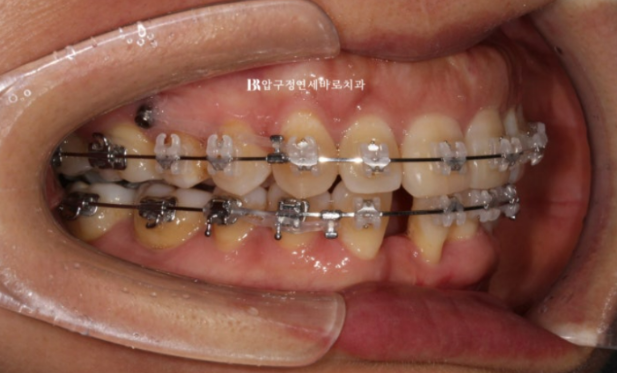

23.10

어느정도 배열이 잡힌 후에 나머지 앞니 1개를 더 뺍니다.

발치한 빈 공간에는 환자분의 품위 유지를 위해 가짜 이를 달았고